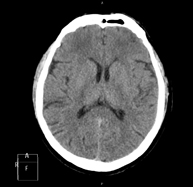

- TC Cráneo

Prueba radiológica que consiste en obtener imágenes del cráneo de alta definición anatómica (tronco cerebral, cerebelo, cerebro, calota craneal, etc.), mediante el empleo de un equipo de TC (Tomografía Computarizada).Indicaciones: traumatismos, cefalea, trastornos de la memoria, pérdida de fuerza súbita en una extremidad o mitad del cuerpo. - TC Cuello